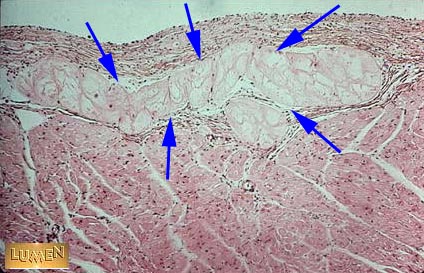

Purkinje Fibers